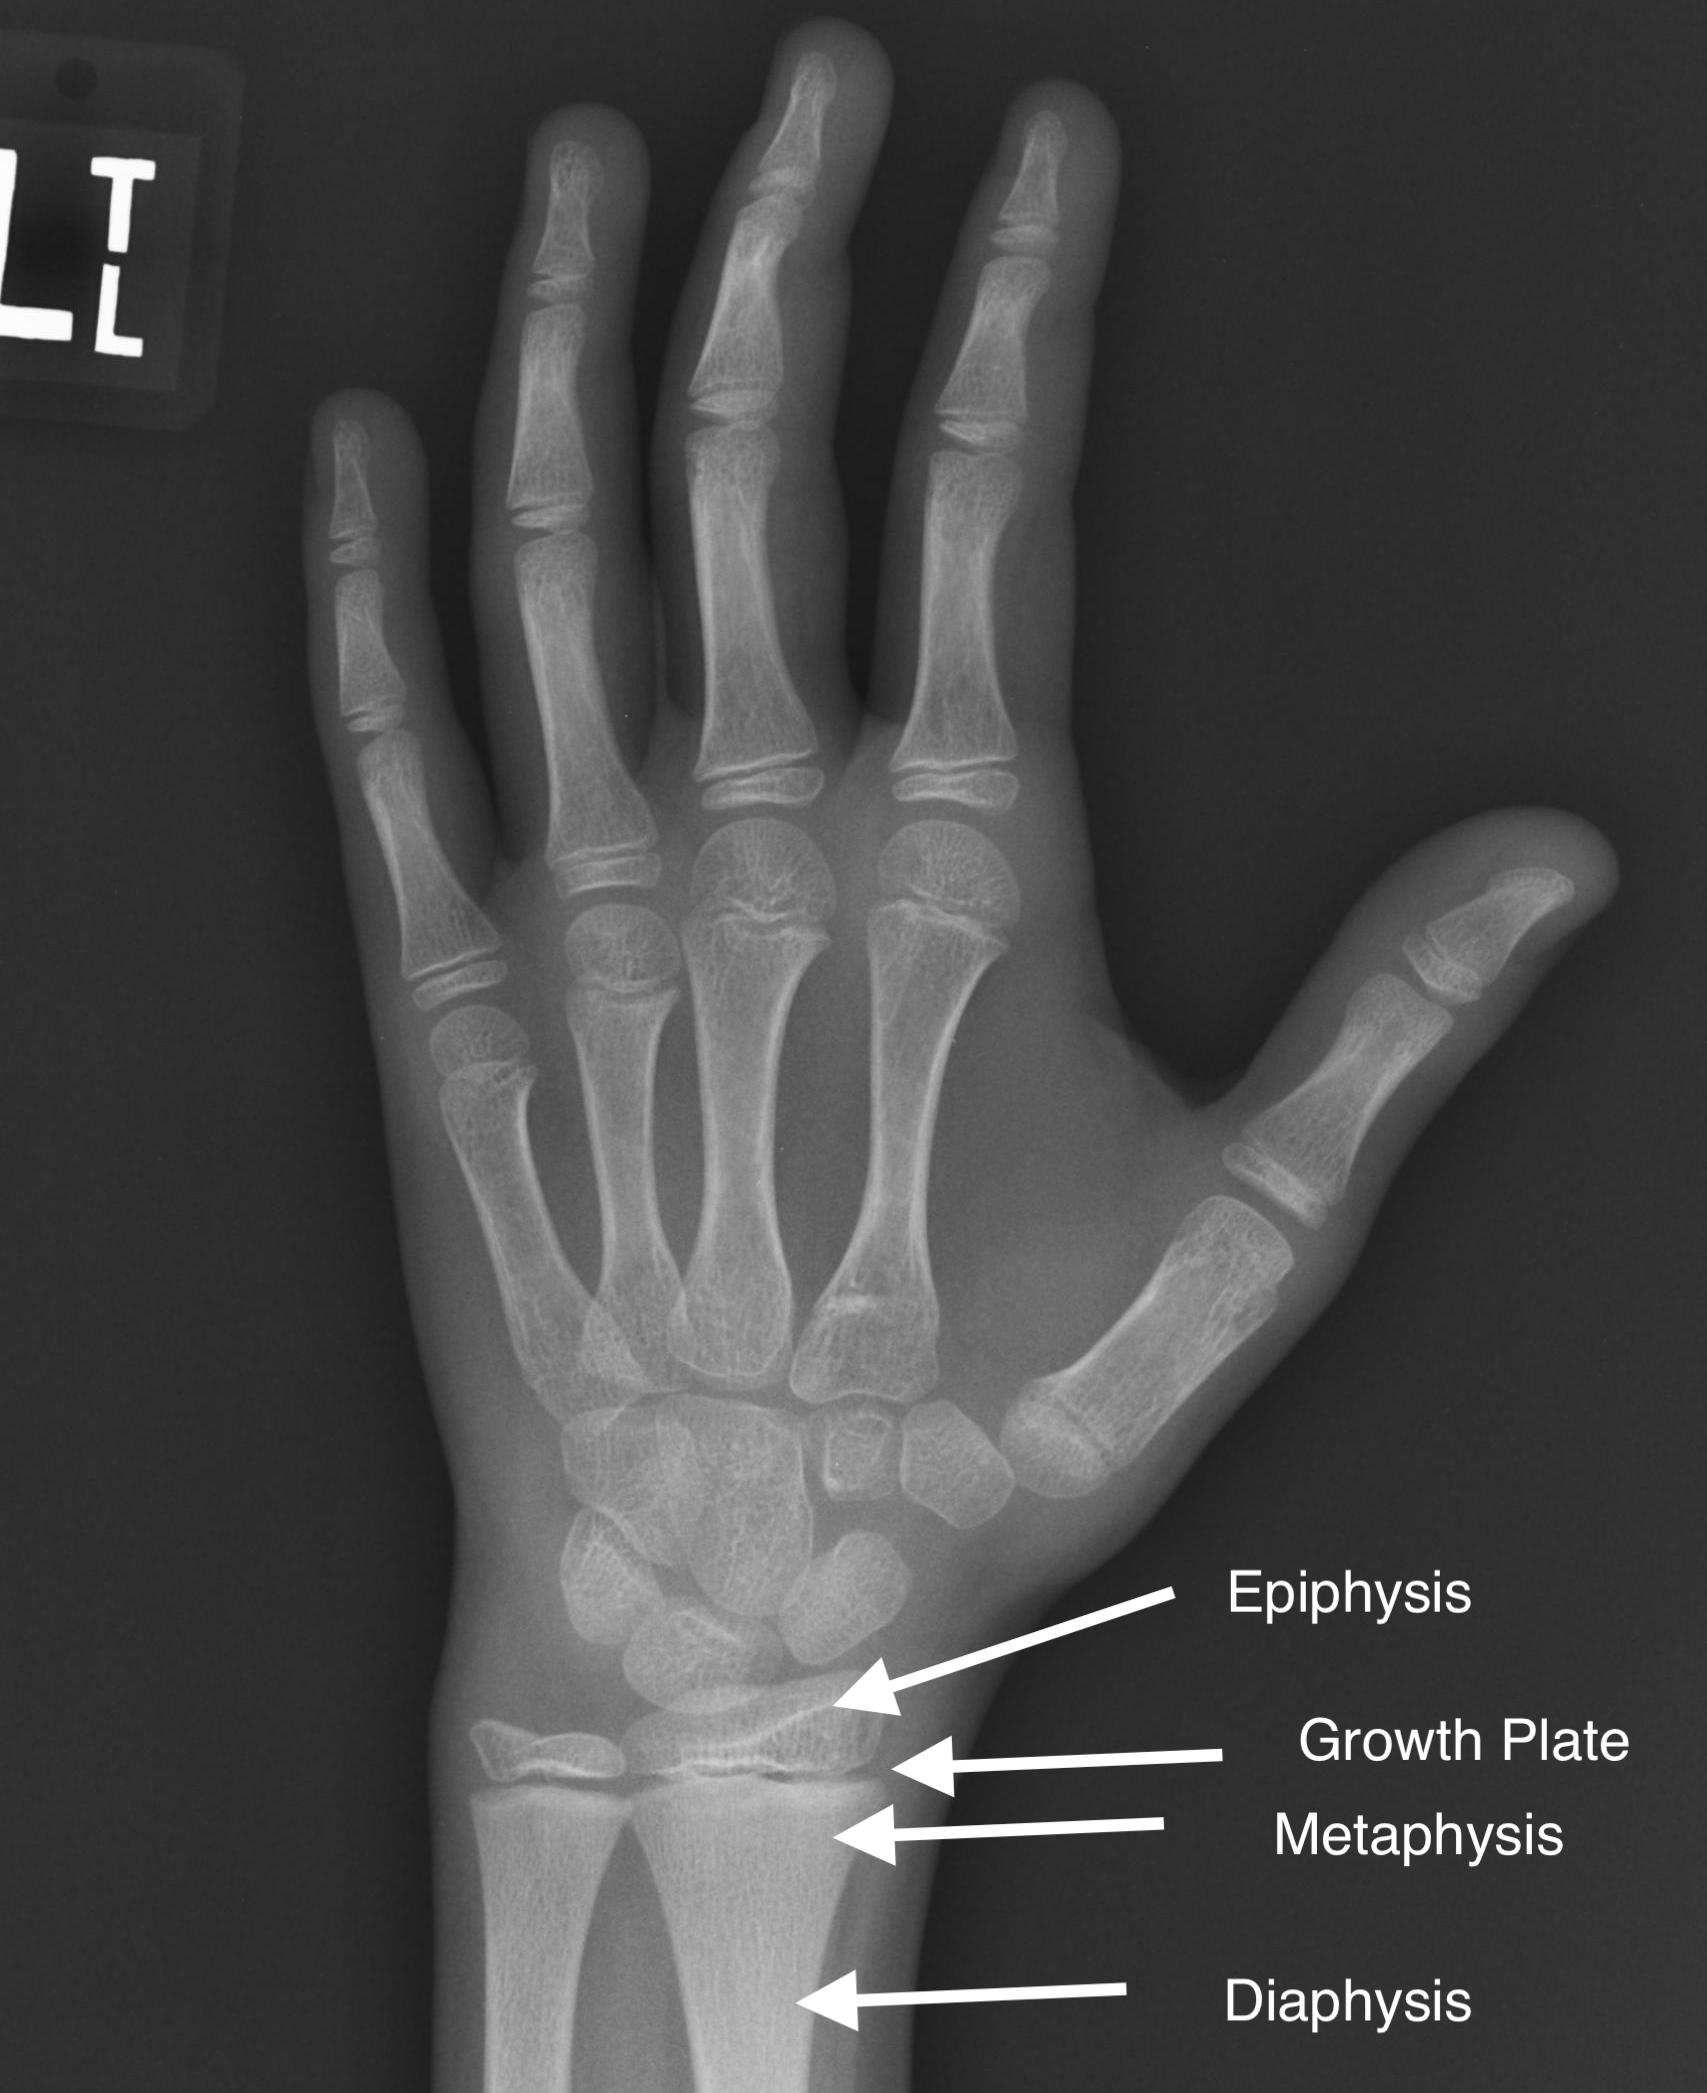

When estimating the age of subadults from bones, we look at the process we call epiphyseal fusion (FIG 1). When humans (and other animals, for that matter) are born, most of their bones consist of many more pieces than in adulthood, and some bones (such as some wrist and ankle bones) are not even present yet. In the arm and leg bones, the main shaft of the bone is separated by a growth plate from what we call an epiphysis, a piece that forms the joint end and joint surface of the bone. In addition to the limb bones, epiphyses are also present in the vertebrae, and the bones of the pelvic and shoulder girdles. As we age, the epiphyses fuse to the main part of the bone on a fairly regular schedule. Understanding the timing of which epiphyses fuse at what age can provide an estimate of an age range for an individual. For example, the humeral head (the part of the upper arm bone that makes the shoulder joint) fuses to the shaft of the humerus between 16 and 23 years of age (Schaefer et al., 2009). If the epiphysis is not attached at all, the individual is most likely younger than 16, and if the epiphysis is fused and there is no trace of the fusion process anymore, the individual is most likely older than 23. There are also established sequences that describe the order in which an individual is expected to fuse, though one has to keep in mind there is always variability among individuals and populations (Schaefer & Black, 2007; Lenover & Šešelj, 2018). For example, the distal femur (the part of the thigh bone that forms the knee) is most likely to fuse before the femoral head (Lenover & Šešelj, 2019).

Fig 1: Visual depiction of the bone shaft (diaphysis), growth plate, and epiphysis